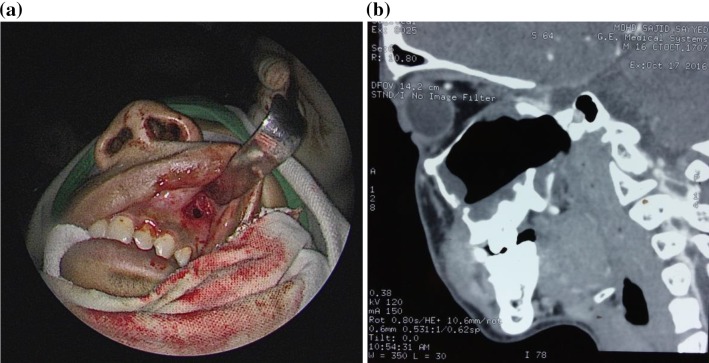

Fig. 1.

a Intra-operative photograph, b post-operative CT scan showing the antral window (port C)